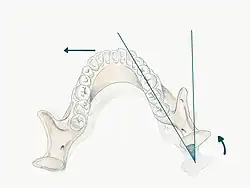

Der Bennett-Winkel ist der in der Horizontalebene gemessene Winkel zwischen der sagittalen Protrusionsbahn und der Mediotrusionsbahn des Kondylus. Im Gegensatz zur Bennett-Bewegung befindet sich der Bennett-Winkel also auf der Balanceseite. Sein Mittelwert beträgt 15–20°, derjenige der Kondylenbahnneigung beträgt 30°. Beides sind Messgrößen für die Kieferbewegungen. Der Bennett-Winkel beschreibt das Ausmaß einer Unterkieferbewegung durch das seitliche Versetzen des Unterkiefers (Mandibula) gegen den Oberkiefer (Maxilla). Er entsteht durch die Projektion zweier Geraden auf die Frankfurter Horizontale.[1] Die Messgröße wird bei der Herstellung von Zahnersatz in einem Artikulator benötigt.

Die Bennett-Bewegung [engl.: Bennett’s movement] ist das seitliche Versetzen der Laterotrusionskondylen während einer Lateralbewegung des Unterkiefers.[4]

Der Kondylus der sogenannten Laterotrusionsseite (Arbeitsseite) erfährt eine progressive seitliche Verschiebung. Diese Bewegung wird als Bennett-Bewegung bezeichnet. Der Kondylus dreht mit einer leichten seitlichen Verschiebung in die Bewegungsrichtung.[5]

Gleichzeitig zur Bennett-Bewegung des Laterotrusionskondylus erfährt der Mediotrusionskondylus eine Bewegung nach ventral, kaudal und medial.

Es kann jedoch auch zu einer unmittelbaren, sofortigen Seitenverschiebung des Mediotrusionskondylus kommen, bevor dieser nach vorne wandert. Man spricht man von einem Immediate side shift. Erfolgt die Medialbewegung des Mediotrusionskondylus hauptsächlich zu Beginn der Vorwärtsbewegung, handelt es sich um ein Early side shift und ist die Medialbewegung auf die ersten 4 mm der Vorwärtsbewegung gleichmäßig verteilt, spricht man von einem Distributed side shift.[1]